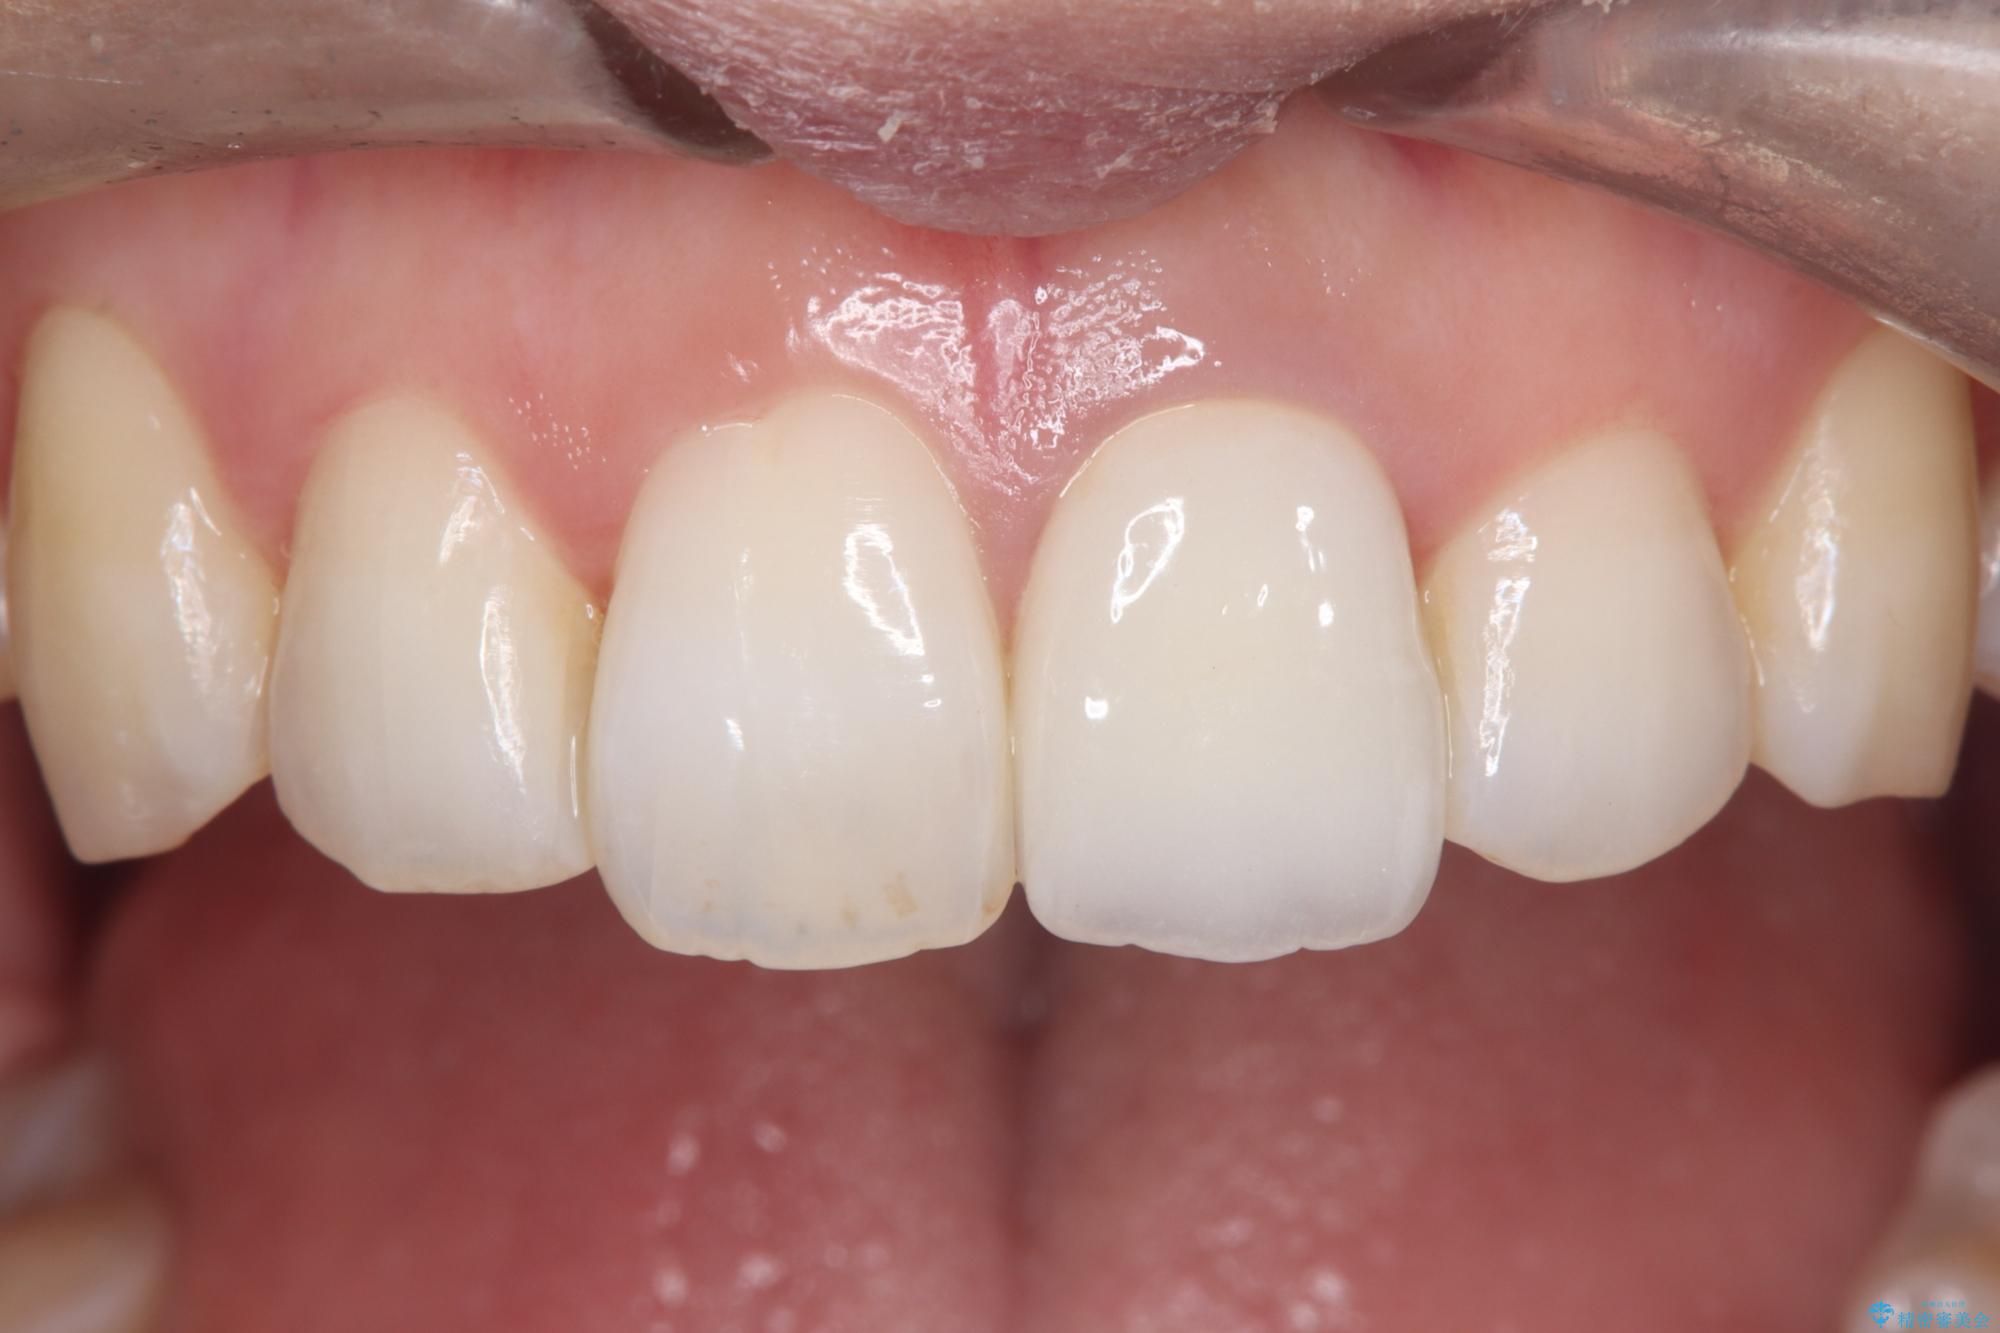

そこで、まずは土台を外して根の内部をきれいにする再根管治療を行い、基礎をやり直した上で、透明感の高いオールセラミッククラウンで被せ直す治療計画を立案。単に白くするだけでなく、再発を防ぎ、長期的に美しい状態を保つことを目指しました。

オールセラミッククラウンによる修復: 最終的な被せ物には、一切の金属を使用しないオールセラミックを選択。隣の天然歯と色調や透明感を精密に合わせることで、どこを治療したかわからないほど自然な仕上がりとなりました。